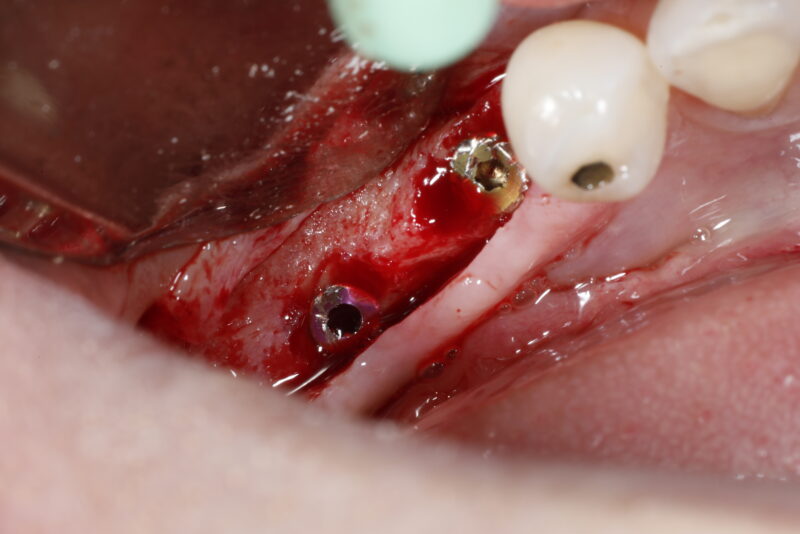

• Two implants were placed. One immediate implant and one implant adjacent on a healed site along with simultaneous ridge augmentation. Implants were covered and primarily closure achieved using PTFE sutures.

This was how the patient presented three weeks post operative for check up and suture removal. What would you do and what are your…

Read more